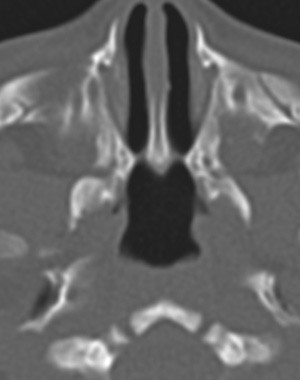

Nyfødte barn er nesepustere, og bilateral koanalatresi vil medføre dramatisk respirasjonsbesvær rett etter fødselen. Diagnosen koanalatresi mistenkes hvis man ikke klarer å føre en sonde gjennom nesen og videre til epipharynx. Endelig diagnose stilles med CT-undersøkelse (fig 3). Et barn med bilateral koanalatresi bør opereres raskt (14). Det er imidlertid risiko for restenosering samt endret vekst av ansiktsskjelettet etterpå.